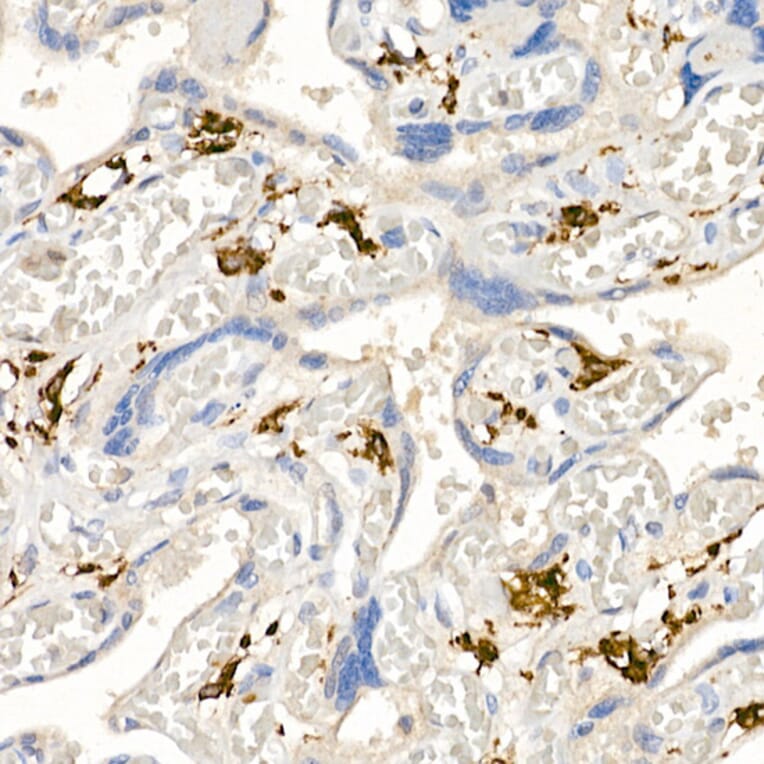

Immunohistochemistry analysis of paraffin-embedded human placenta using Anti-CD163 Antibody (A17078) at a dilution of 1:50 (40x lens). Perform high pressure antigen retrieval with 10 mM citrate buffer pH 6.0 before commencing with IHC staining protocol.